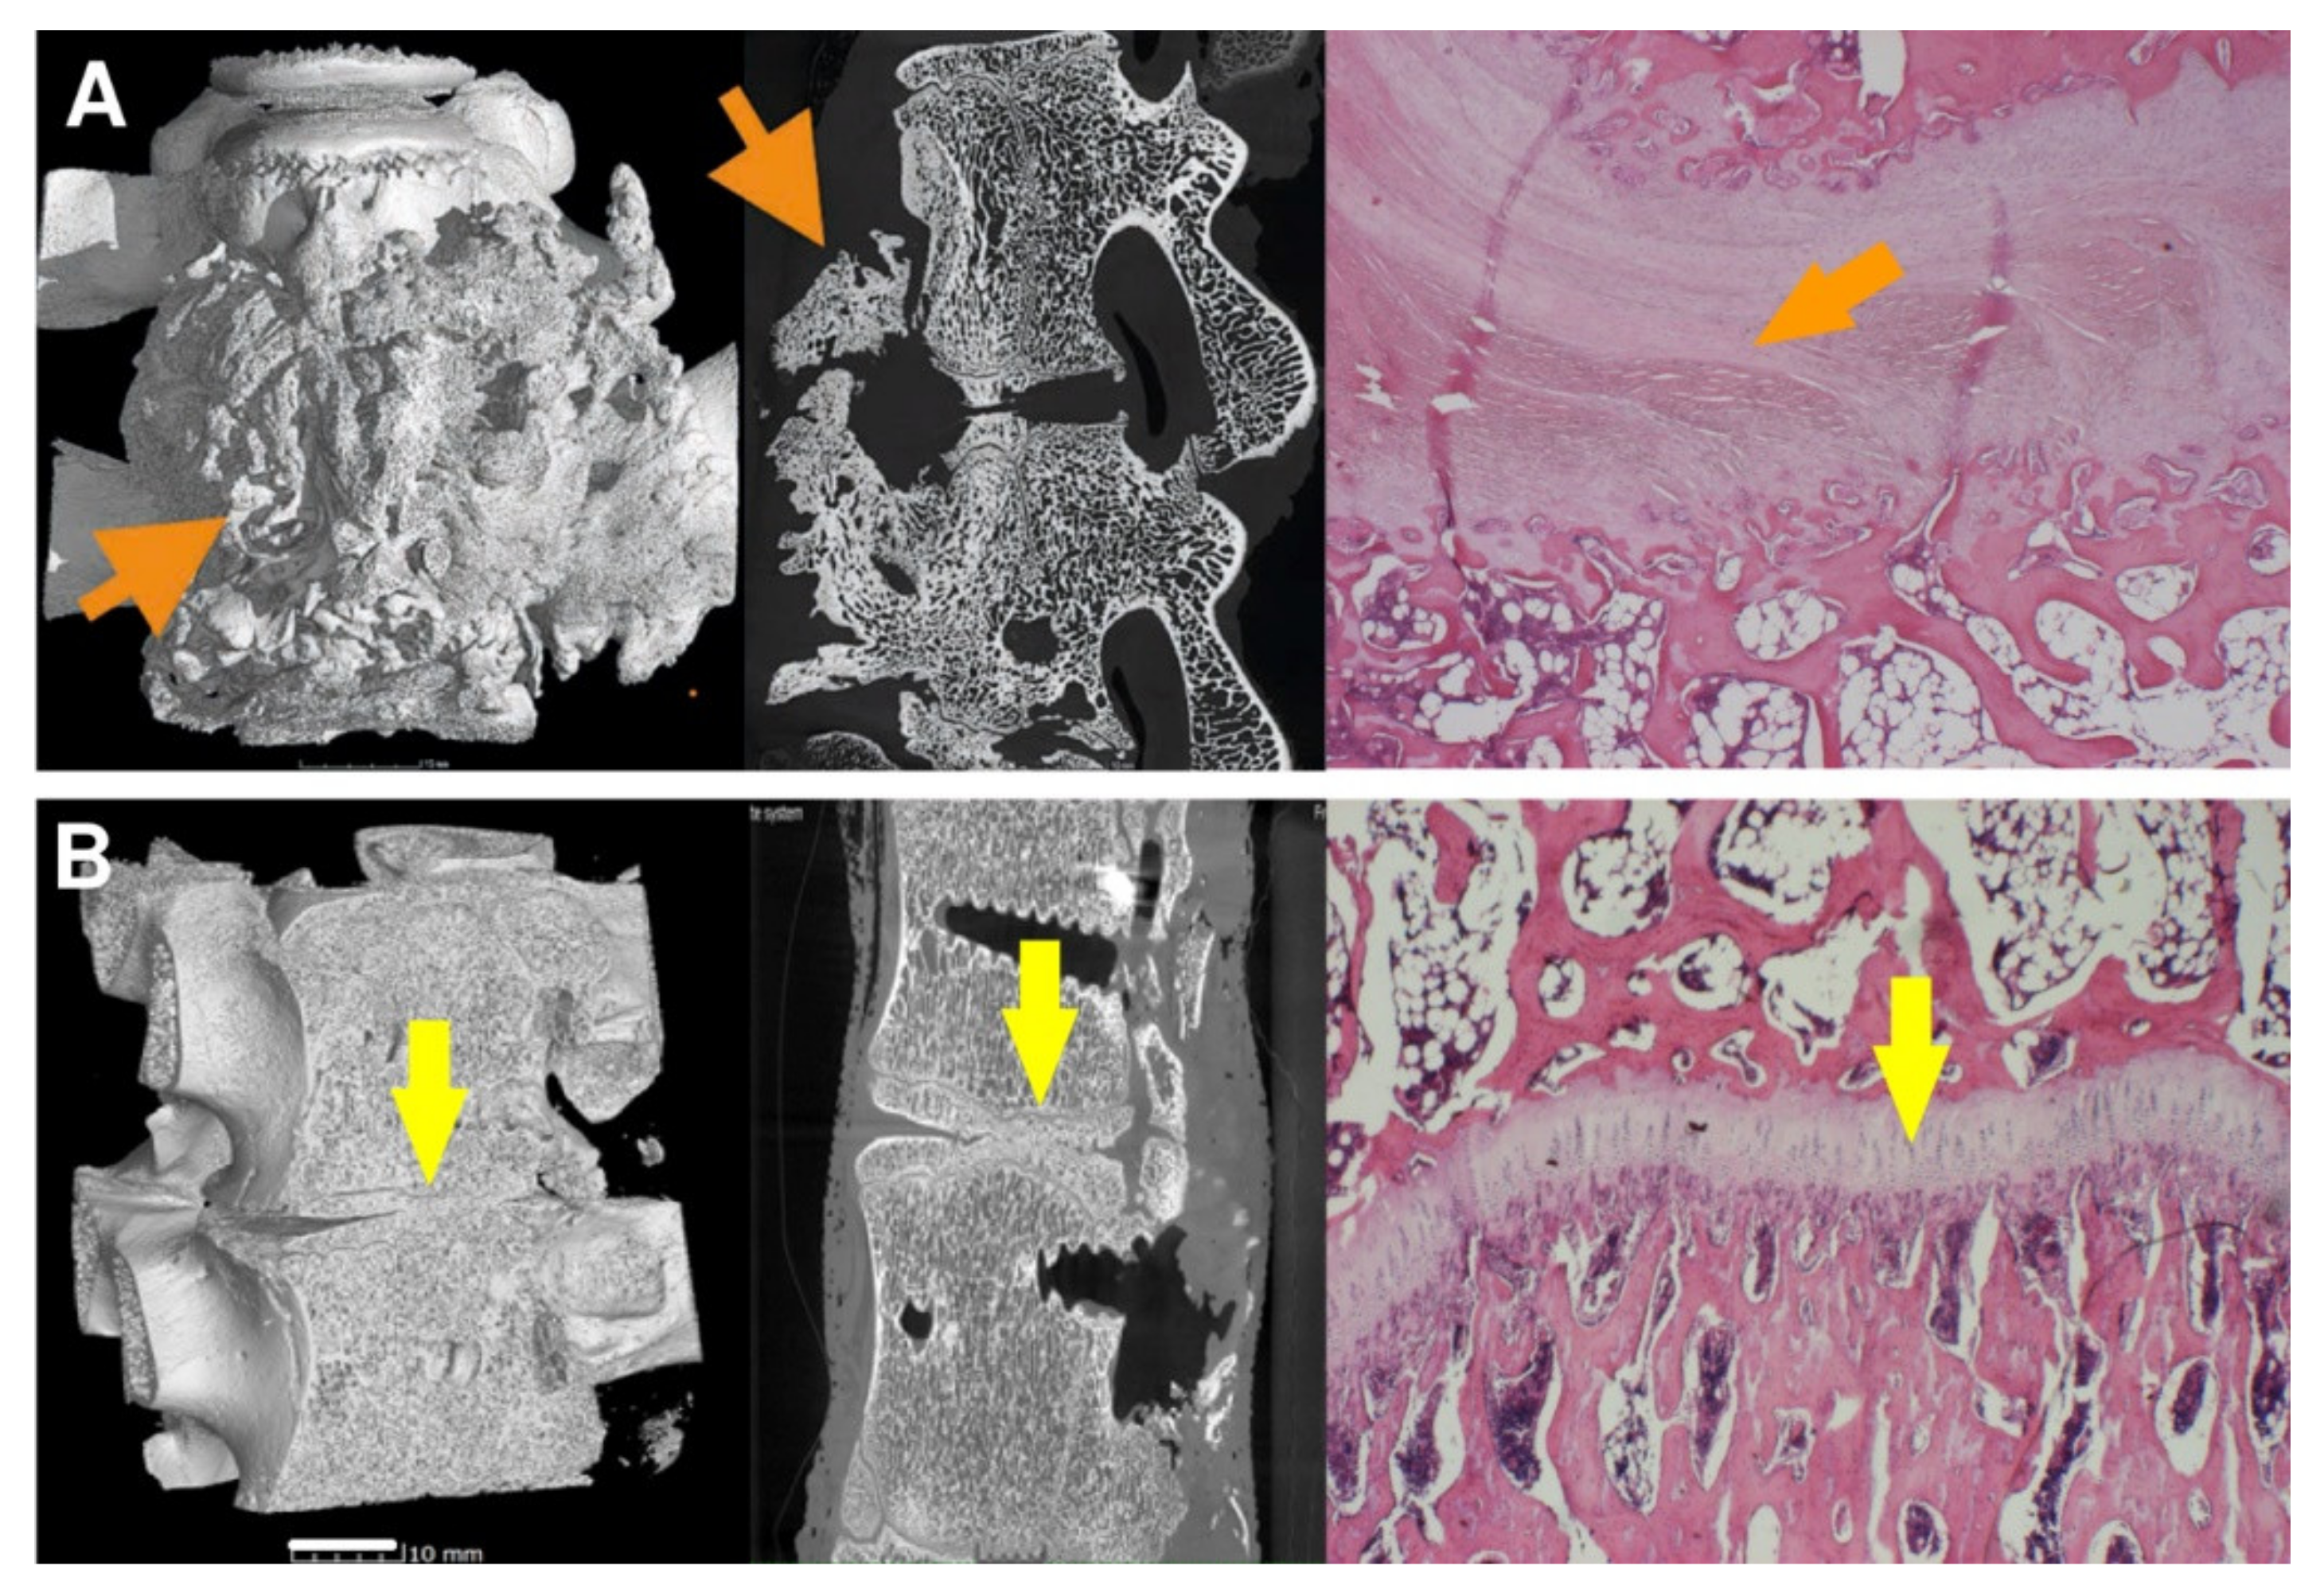

As can be seen from Table 1, the 8-week bone autograft group (subgroup A1) involved three samples, where the vertebras were surprisingly fused within the whole area of the bone graft. The fusion is steady and compact in micro-CT cross-sections. In one case, the bone graft was already fully absorbed exhibiting no fusion at all. However, after 16 weeks, the second group of bone grafts (subgroup A2) displayed a much lower quality of fusion, where the graft was completely absorbed in three cases. The vertebrae fused around the bone graft, and the fusion caused so-called non-union outgrowth around the whole vertebra’s body (Figure 10A). These large outgrowths have mostly affected the motion and bending of the spine. Moreover, intervertebral endplates are missing since they have been absorbed during the interaction with the bone graft. These disadvantages are widespread when a bone autograft is used.

Figure 10.

The vertebrae fusion of cadaveric lumbar spines is presented by micro-CT and histology images after 16 weeks after surgery for subgroups A2 (A) and B2 (B). Left pictures represent micro-CT 3D visualization, the middle images show micro-CT cross-section, and the right ones correspond to the histological images. On the micro-CT images, clearly visible nonunion outgrowth can be seen in Group A2 (autograft) (A, orange arrows), while the bone fusion of the intervertebral areas without connective tissue outgrowth marked with yellow arrows of group B2 (sample with bioresorbable hybrid implant (BHI)) is observed in figure (B). micro-CT images very well corresponded to the histological pictures, where the central fibrous cartilage (light pink) layer is in the middle of the bone tissue (A, right image), whereas endochondral ossification with new bone and without fibrous tissue was formed after BHI implantation (B, right image, yellow arrow). Histological decalcified samples were stained by hematoxylin-eosin to observe the nucleus of the cells (blue-violet), the cytoplasm (pink), collagen connective tissue (light pink), cartilage cells (dark blue), and muscle (red).

As for the 8-week subgroup B1, where BHI was applied, the demonstrated results in Table 1 are very similar to subgroup A1. However, except for one fully absorbed sample, the fusion was mainly generated through/over the scaffold. Clearer are data from the 16-week subgroup B2, where fusions appear only between the bodies of the vertebra, and no large outgrowths were visible around the vertebrae in micro-CT images (Figure 10B). In addition, the intervertebral endplates were still found within the images, and in a few cases, intervertebral plate narrowing was observed.